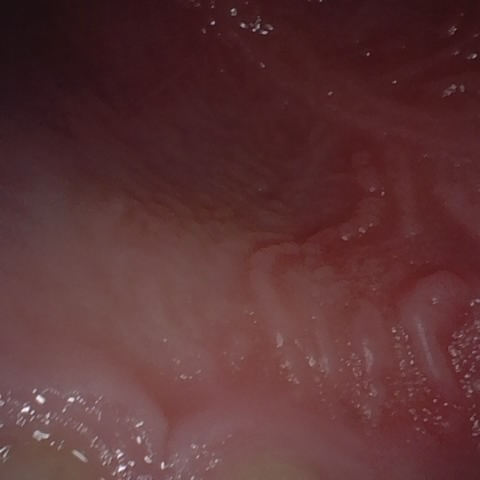

NHD39990

Annotated as "Good"

Original Image Rendering Image